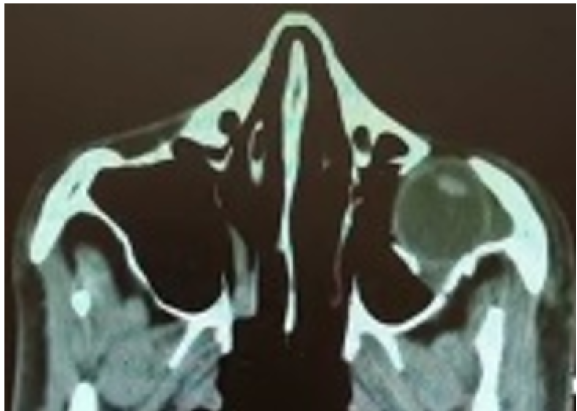

Clinical Image

Traumatic Globe Displacement into the Maxillary Sinus

Ali Sharifi, Arash Daneshtalab, Mahsa Sardarinia, Reza Ataee and Amin Zand. 14(3): 20-23.